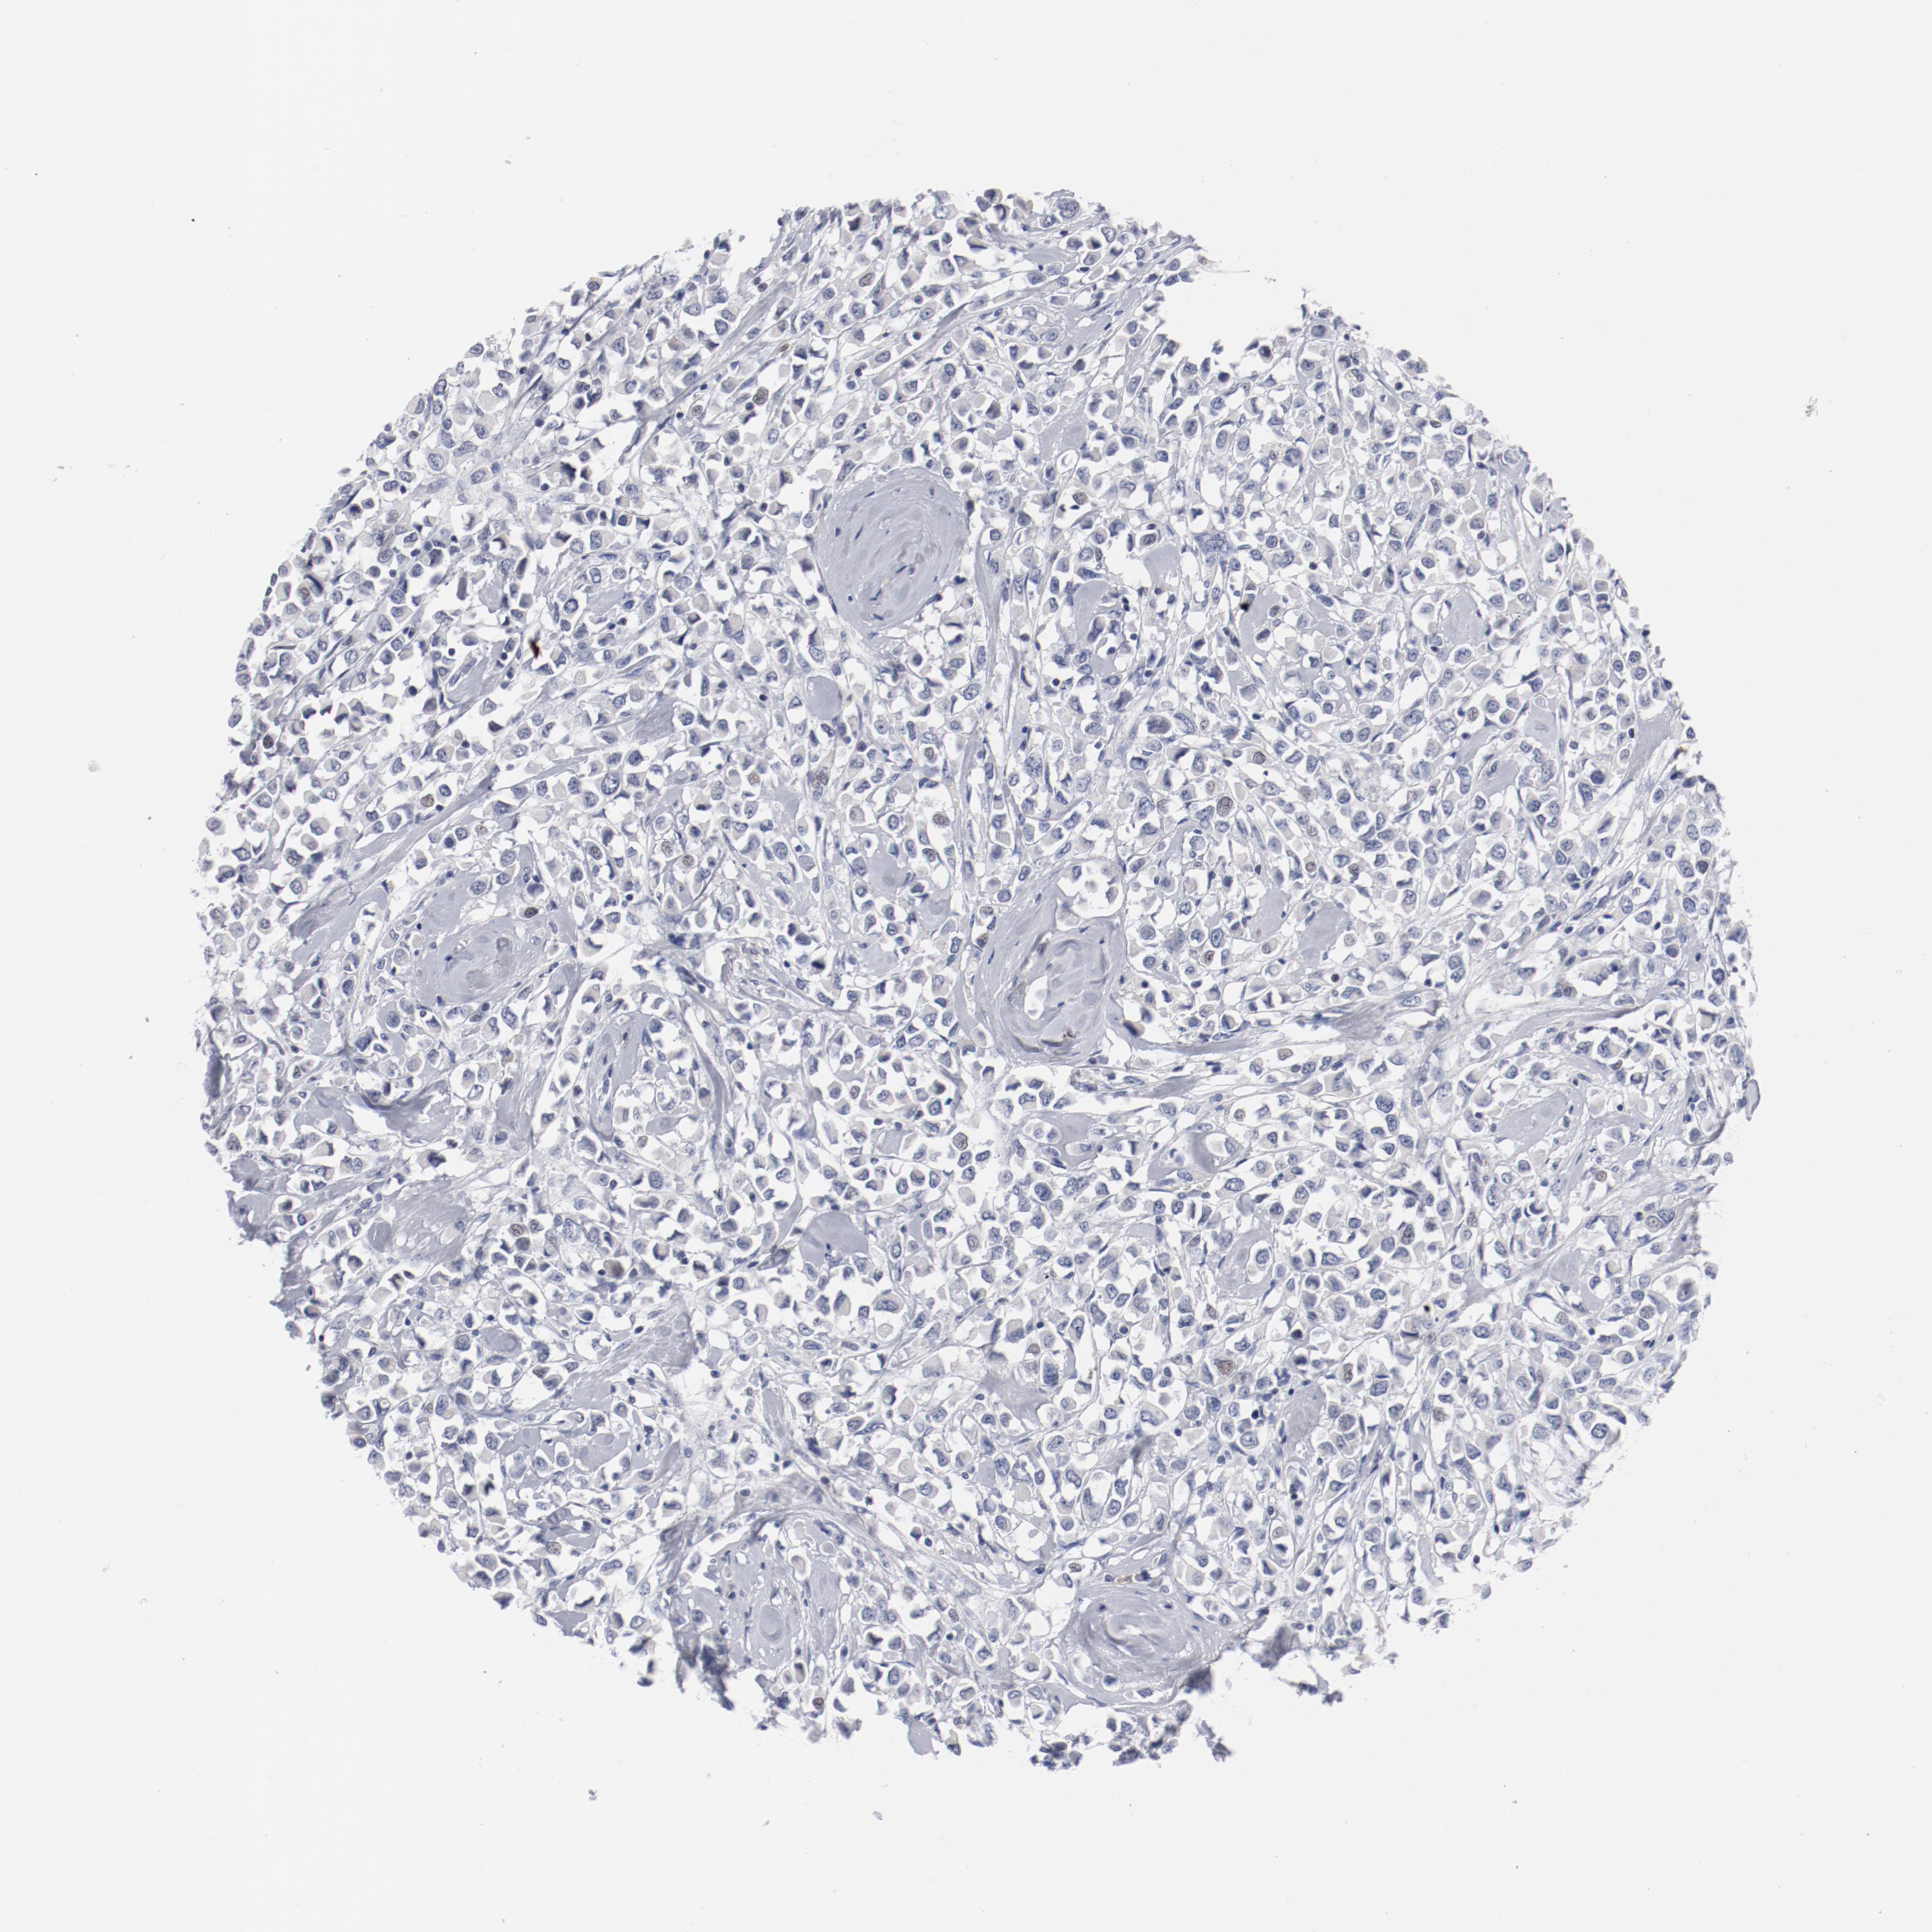

CANCER BREAST CANCER Show tissue menu

BRCA TCGA BRCA VALIDATION PROTEIN EXPRESSION